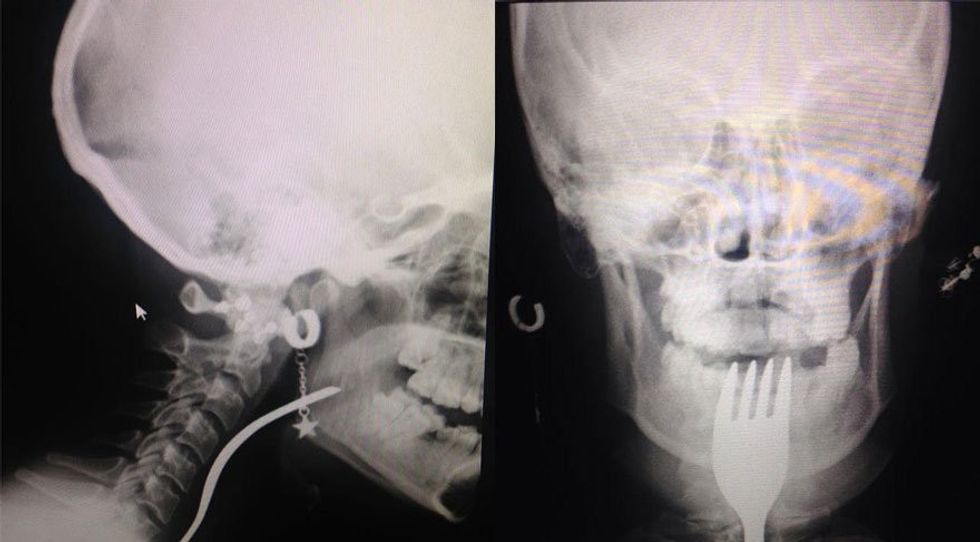

Media raportoi se një 19-vjeçare ka kaluar momente tepër të vështira pasi ka kaluar në fyt pirunin, të cilin po e përdorte për të hequr pjesë ushqimi nga dhëmbët e saj të prishur.

Naciye Ak nga qyteti i Bursës është dërguar me urgjencë në spitalin e qytetit, Uludag, ku i është nënshtruar një operacioni.

Agjencia e lajmeve “DHA’ tha se tashmë gjendja shëndetësore e të resë është e mirë. /tvklan.al